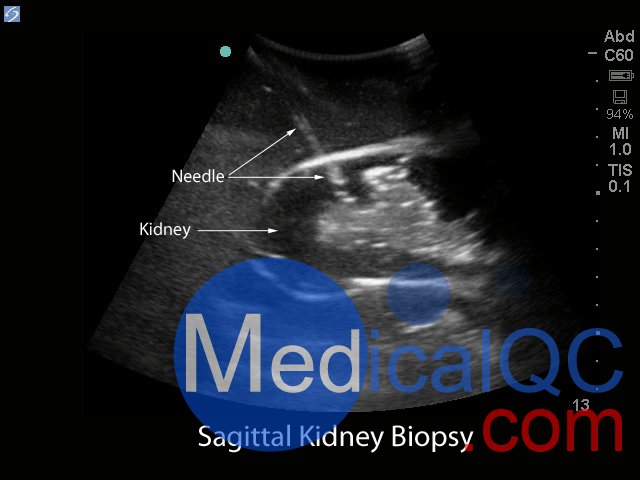

Blue Phantom的經皮腎穿刺活檢超聲訓練模型允許使用芯針穿刺活檢或穿刺穿刺技術重復進行針頭活檢。該模型提供了解剖學上正確的成年男性軀干,其超聲組織模塊包含皮膚,肋骨和右腎以及周圍組織。腎臟的內部和外部結構在其逼真度和成像特性方面極佳,并且包含腎皮質,腎髓質以及主要和次要的花萼。使用與真實人體組織的聲學特征相匹配的Blue Phantom模擬組織構造而成,因此,當您在我們的訓練模型上使用超聲系統時,您將獲得與在臨床環境中對患者進行成像所期望的相同質量。

精通超聲引導下的腎核心活檢或針吸手術

Blue Phantom腎臟活檢超聲訓練模型為用戶提供了極為逼真的超聲成像特征,感覺就像真實的人體組織。Blue Phantom的專利超耐用自我修復組織為用戶提供了較低的擁有成本。除了訓練用戶如何利用超聲波對腎臟成像外,用戶還可以對模型執行兩種類型的操作:

核心針穿刺活檢程序。使用超聲引導的腎臟活檢模型進行核心針頭活檢的臨床醫生期望從模型中去除組織樣本。取出核心組織樣本后,腎臟中會留有一個空氣,其大小相當于核心樣本的大小。用戶可以期望在腎臟需要更換之前將核心活檢樣本取出30次(腎臟很容易取出,這樣未使用的上腎臟可以旋轉到下極位置)。

針抽吸程序。使用超聲引導的腎臟活檢模型進行針抽吸手術的臨床醫生可以期望在使用18 – 21號針頭時具有巨大的實用性。Blue Phantom的專利自修復超耐用薄紙可重復使用。當用戶使用鋒利,彎曲的針頭時,將獲得最佳的愈合效果。

超聲成像和程序技能包括;使用超聲系統控制,換能器定位和移動,識別腎解剖結構,在腎活檢期間避免肋骨出現,避免肋骨出現,使用超聲將目標對準腎活檢的適當位置并執行超聲引導的腎活檢程序。使用配置了適當的腎臟活檢換能器的任何超聲成像系統,此超聲動手訓練模型將表現良好。這種超聲體模模型非常適合包括腎臟科,介入放射學,外科手術,外科手術訓練計劃,超聲訓練計劃,模擬中心,外科技能中心,醫學教育設施,腎臟活檢設備制造商和超聲制造商進行超聲教育和演示的專業。